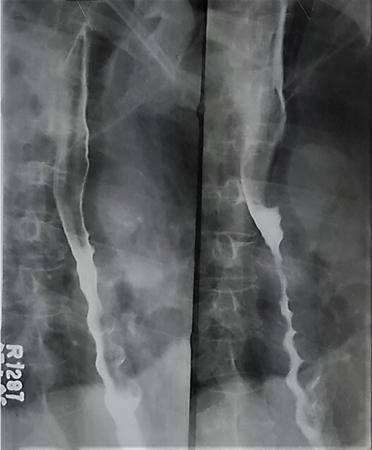

Fig. 7.4.2.1Barium swallow in a 50-year-old male with history of progressive dysphagia of one-year duration. Source: (Image courtesy Dr Vijinder Arora, Nijjar Scan & Diagnostic Centre, Amritsar, India.) Radiological Technique: Barium swallow (barium pharyngography).

A barium-filled outpouching is seen posterior to the cervical oesophagus, with the neck of the pouch at the level of C5–C6 (just cranial to the anticipated position of the cricopharyngeus muscle).

Principal Diagnosis: Zenker’s diverticulum.